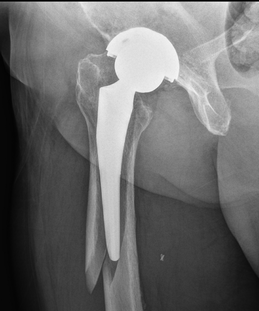

Hip replacement surgery is a medical procedure in which a surgeon removes damaged parts of a hip joint and replaces them with artificial components. Artificial joints are typically constructed from metal, and they are designed to replicate the natural movement of the hip. The goal of this procedure is to address joint damage and help individuals regain mobility when daily life is affected by hip pain. Here are some innovations in hip replacement techniques and materials:

The selection of materials is a fundamental aspect in the design and long-term performance of hip implants. Developers often prioritize new metal alloys because of their durability and compatibility with the human body. Cobalt-chromium and titanium alloys remain widely used, valued for their strength, ability to resist corrosion, and lightweight properties. Advanced alloys include other metals to further enhance wear resistance and reduce the risk of metal ion release. Titanium-niobium alloys display flexibility and compatibility.

Biocompatible coatings are thin layers of material applied to the surface of hip implants that come in contact with bone. Hydroxyapatite is similar in composition to human bone and encourages the body to accept and bond with the artificial joint. This process, called osseointegration, helps stabilize the implant and supports long-term strength at the bone-implant interface.

Other coatings, such as titanium plasma spray, are used to roughen the surface and further enhance the connection between implant and bone. The goal is to create an environment that allows bone tissue to grow safely onto the implant surface. These coatings are particularly relevant for patients who require greater initial stability or have conditions that affect bone health.